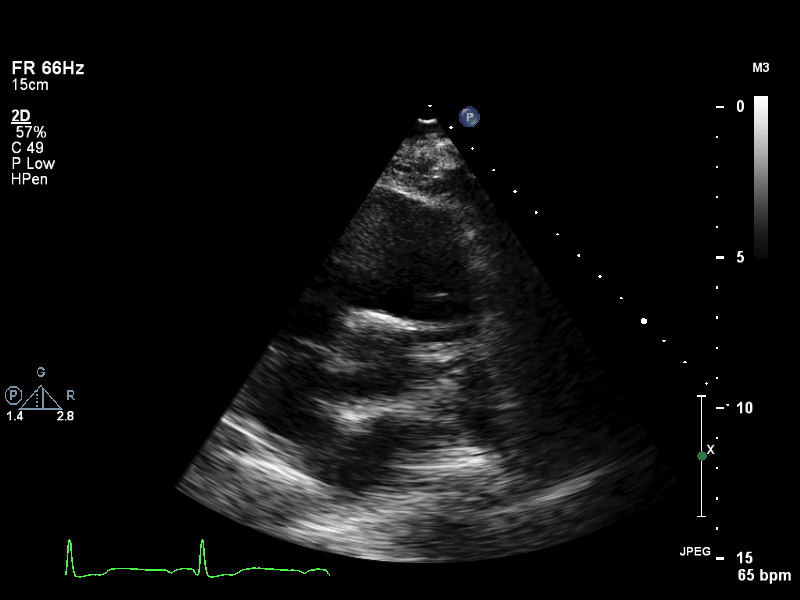

ImageView NameDescription

a4ch-full a4ch-full Apical 4-chamber showing the full depth of all four chambers (no LV/RV focus)

a4ch-ias a4ch-ias Apical 4-chamber, focused on the inter-atrial septum

a4ch-la a4ch-la A4CH with Doppler near MV/LA or 2D covering full LA, not full LV

a4ch-lv a4ch-lv A4CH covering the whole depth of the LV, not the whole depth of the LA

a4ch-ra a4ch-ra Apical 4-chamber focused on the right atrium, or colour Doppler on TV/RA

a4ch-rv a4ch-rv Apical 4-chamber focused on the right ventricle